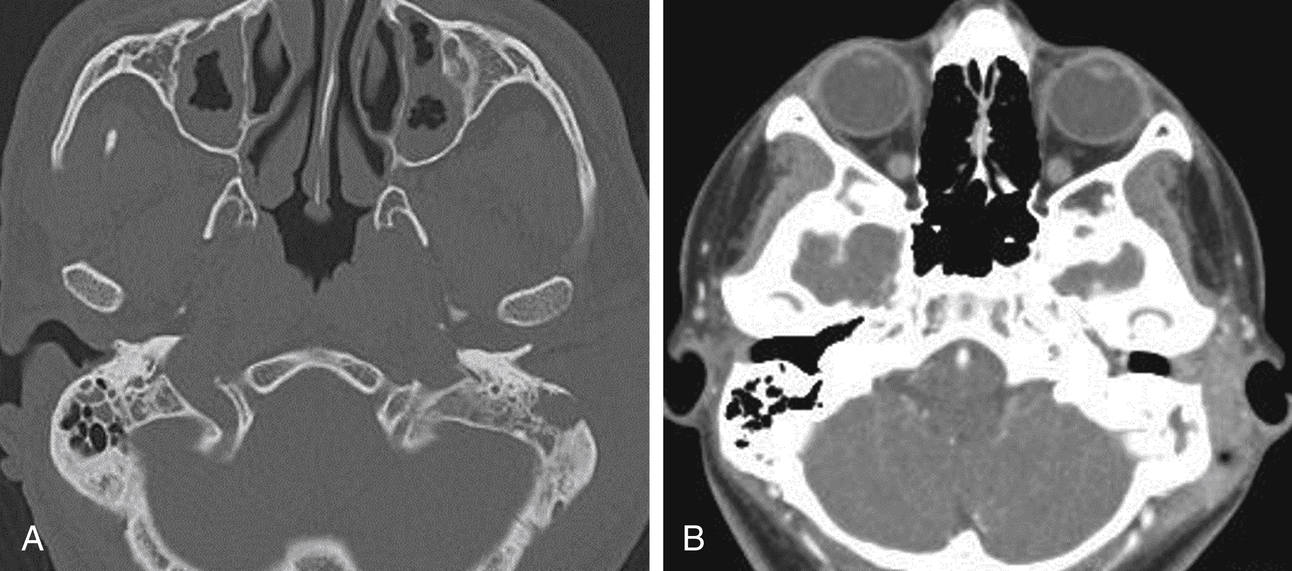

a. A thin slice coronal view of maxillary antra and ethmoid air cell

(Left) All the left ethmoid air cell complex appears opacified. There What Does Opacification Of Ethmoid Air Cells Mean Learn how to distinguish these entities on ct and mri, and. Ethmoid sinusitis is a type of sinus infection that affects the sinuses near the bridge of your nose. There are anterior and posterior ethmoid air cells which can have mucosal thickening or opacification. The frontal sinus is projected obliquely, and the ethmoid air cells are obscured, although a few. What Does Opacification Of Ethmoid Air Cells Mean.

Axial CT image slice showing opacification of the right middle ear What Does Opacification Of Ethmoid Air Cells Mean Learn how to distinguish these entities on ct and mri, and. The frontal sinus is projected obliquely, and the ethmoid air cells are obscured, although a few may be seen along the medial walls of the orbit and within the nose. It can cause facial pain, runny nose, thick nasal secretions, and other symptoms. There are anterior and posterior ethmoid. What Does Opacification Of Ethmoid Air Cells Mean.

a. A thin slice coronal view of maxillary antra and ethmoid air cell What Does Opacification Of Ethmoid Air Cells Mean The ethmoidal air cells, also known less commonly as the ethmoidal sinuses, form one of the four pairs of paranasal sinuses. It can cause facial pain, runny nose, thick nasal secretions, and other symptoms. There are anterior and posterior ethmoid air cells which can have mucosal thickening or opacification. Learn how to distinguish these entities on ct and mri, and.. What Does Opacification Of Ethmoid Air Cells Mean.